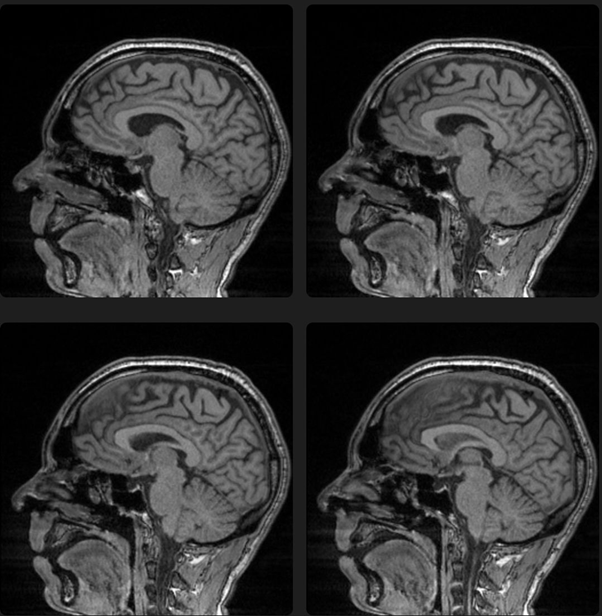

After that, the patient was referred to a neuroendocrinologist for a better diagnostic evaluation of Diabetes Insipidus, which was discarded after specific exams. After two weeks, the patient decided to stop taking risperidone because it was associated with dehydration and weight loss, in addition to not returning for consultation on the scheduled date. After a week, the patient evolved with worsening psychotic symptoms, mystical delusions, insomnia and irritability that triggered a suicide attempt with a stab wound and a sharp wound in the cervical region. He was referred to emergency and later to psychiatric hospitalization where he remained for 22 days. The patient was diagnosed with bipolar I disorder in a manic episode with psychotic symptoms. There was no family history or past history of psychiatric problems and no history of substance abuse. His diagnosis was bipolar disorder in a mixed episode. Magnetic resonance imaging (MRI) of the pituitary suggested an empty sella (Figure 1). Vague hypodensity is seen in the pituitary fossa. The pituitary is enlarged with remodeling of the pituitary fossa. Heterogeneous with high T1 and low T2 signal, particularly on the right

Figure 1 Pituitary apoplexy.